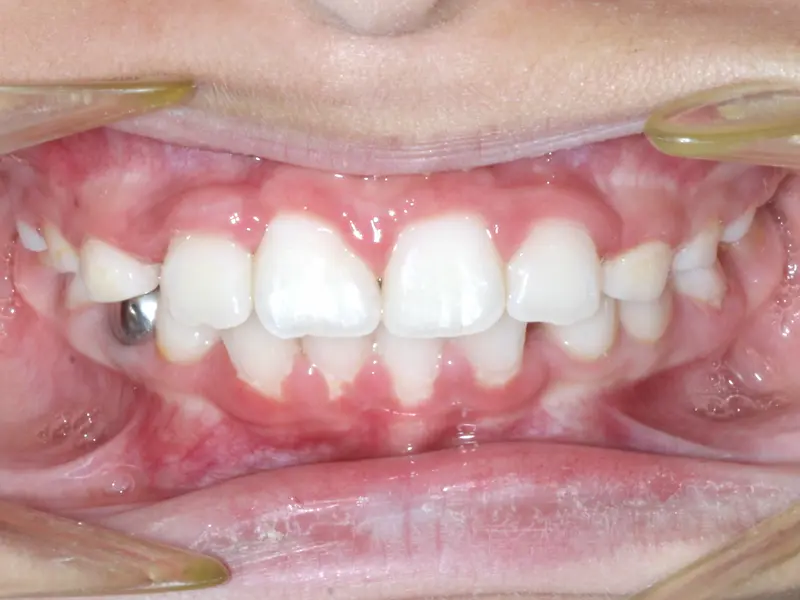

The Diagnosis

Severe crowding with blocked-out permanent teeth. The jaw size was insufficient to accommodate the erupting adult teeth, leading to significant rotation and displacement.

The Engineering

By intervening early, we utilized rapid palatal expansion to develop the arch width. This created the necessary space for the permanent teeth to erupt naturally, avoiding the need for future extractions.

After treatment: The Expansion Phase

After